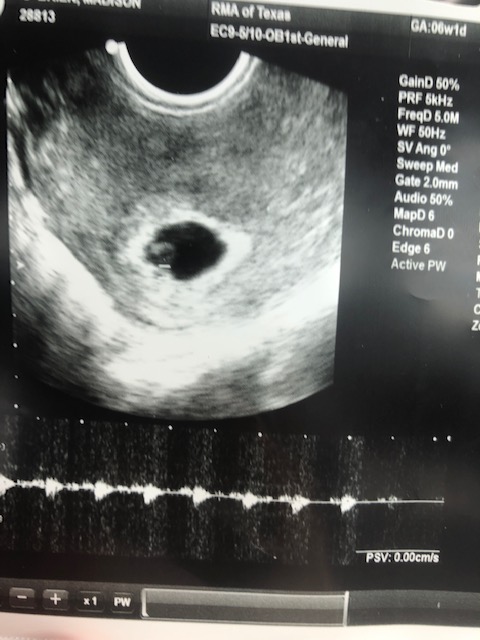

6 Weeks: We had our first ultrasound on Sept. 17th at our fertility clinic in San Antonio. We couldn’t really see much, but we did hear a heartbeat which is probably the most reassuring sound I’ve heard in my life. This was out last appointment at the clinic and we are officially graduated! The nausea has become constant although thankfully no vomiting yet. I am also beyond tired and it takes every ounce of energy to just function at work. I have begun taking a nap during lunch and a nap before rehearsals and I am still in bed by 8:00p.m.